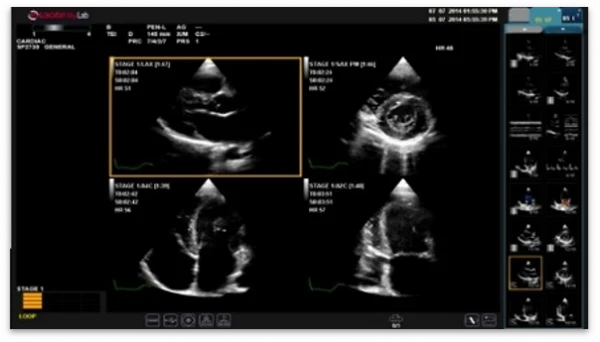

Stress ekokardiyografi uchun Stress Echo, shu jumladan kontrast